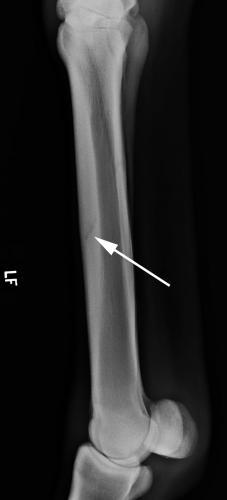

This is a picture of bucked shins.

“Bucked shins” are part of the disease complex known as dorsal metacarpal disease. Bucked shins is a painful, acute periostitis on the dorsal surface of the third metacarpal bone. It is seen most often in the forelimbs of young Thoroughbreds (2-yr-olds) in training and racing, and less commonly in Standardbreds and Quarter horses. Bucked shins may be the result of high-strain cyclic fatigue caused by excessive compression on a bone that has not remodeled enough to tolerate the stress placed on it. Stressed bone forms a new layer of bone at the point of stress. This new bone is weaker and, in the process of rapid bone formation, the periosteum becomes elevated and inflamed.

This injury on the third metacarpus is most commonly seen in which patient?

A) 2 wk old foal that has been running after its dam

B) yearling colt that has just been castrated

C) 2 yr old race horse in training

D) 8 yr old mare quarter horse used for barrel racing

E) none of the above

C) 2 yr old racehorse in training